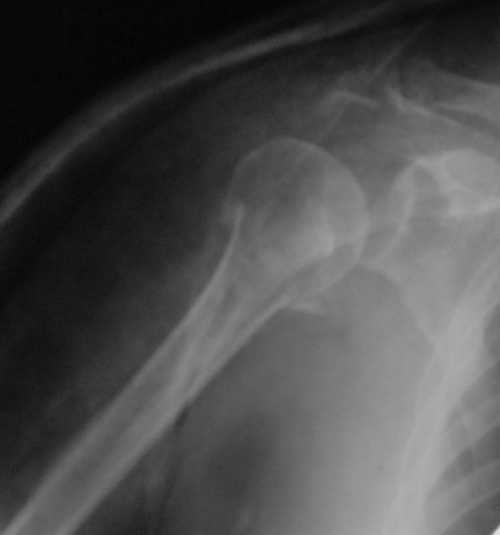

Судя по снимкам головка ротирована,успех закрытой репозиции, на мой взгляд, сомнителен, надо оперировать.

Судя по Р-граммам имеется оскольчатый перелом головки плеча. Во время открытой репозиции имеется большой риск "развалить" перелом, что значительно ухудшит кровоснабжения отломков. А так, на мой взгляд контакт м\у отломками достаточный, не смотря на наличие ротационного смещения головки думаю лучше продолжать консерватикное лечение. С уважением.

Судя по снимкам еще имеется перелом головки плеча, и чрезкостный отрыв вращательной манжеты. Для уточнения характера перелома не иешало бы сделать КТ. Если вести консервативно, то после сращения перелома будет ограничение движений в суставе не устраивающее больную. Я склоняюсь к оперативному лечению( накостный остеосинтез Т- Г образная пластина, лучше LCP для проксимальног плеча, обязательно подшить на место манжету).

В соответствии с работами Neer данный перелом можно классифицировать как однофрагментарный, так как нет диастаза более 1 см и углового смещения более 45 градусов - такие переломы лечатся консервативно. Рентген контроль каждые 10 дней- если смещение не увеличивается, то через 3-4 недели разработка движений в суставе

Уважаемый Сергей! Вы правильно написали критерии, но недооценили степень смещения в переломе хирургической шейки. Посмотрите ещё раз, это Two part fracture.